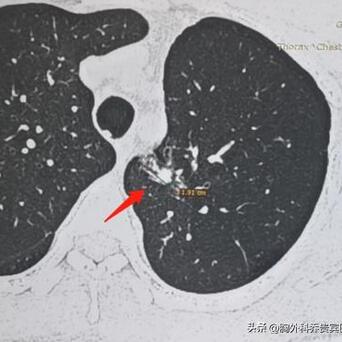

长这样的肺结节,很容易被误诊成肺癌!要是手术切了就太亏了。这位患者在1年前,就体检查出了一个肺混合磨玻璃结节,先是上网查,说是“肺混合磨玻璃结节大多数是肺癌”,再加上看了当地的医生,也说考虑是癌症。

但我看了他的CT片,这个肺结节长得比较散,并不是圆溜溜的,类似长条状的病灶,从多年临床经验来看,考虑炎症的可能性大,所以我就建议他先吃消炎药后,3个月再复查。

后来看了他复查的片子,病灶已经变淡了,别的地方还残留一些小小陈旧炎症结节,可能一辈子都不会消失,但只要定期复查就可以了。